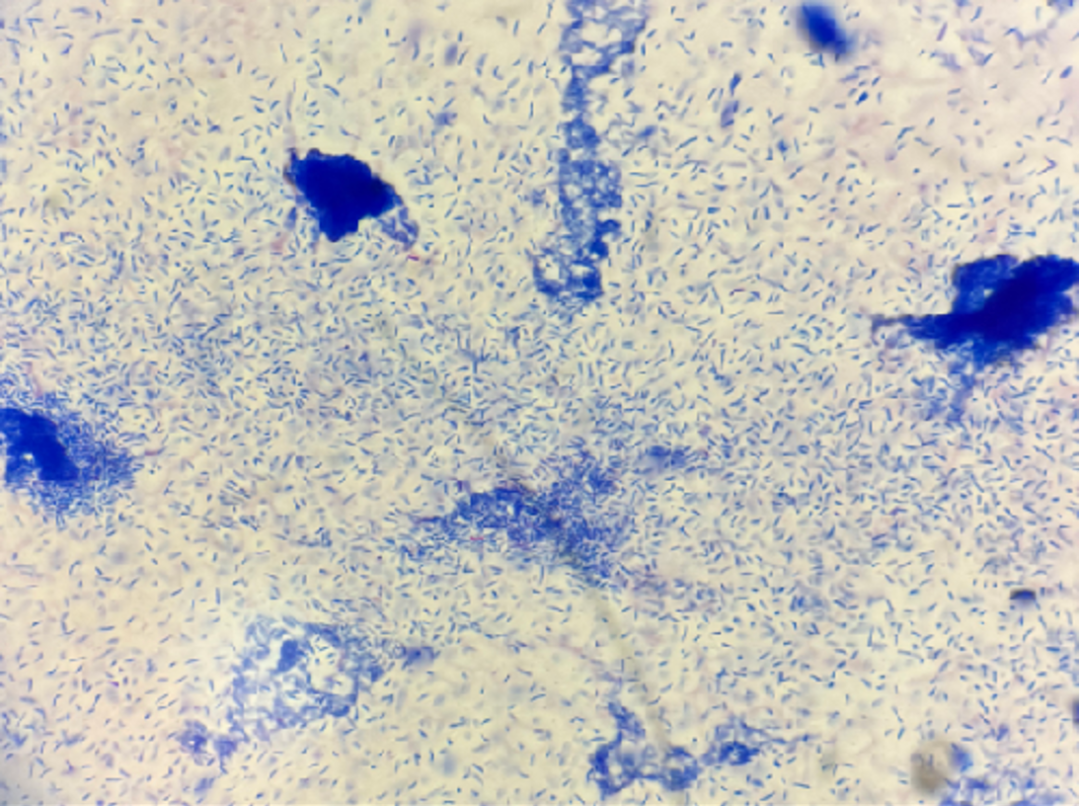

弱抗酸染色仅少量呈现为抗酸阳性。(图5)

104.png